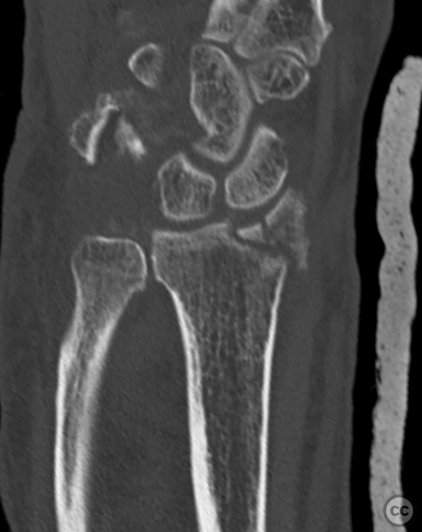

Clinical and radiological findings:  A 72-year-old female sustained a multifragmentary, dorsally displaced distal radius fracture after a fall down stairs. Initial reduction revealed a 180-degree flipped fragment of the volar ulnar articular margin, unreducible by closed means. There was no mention of associated neurovascular compromise or open injury. Radiographs and intraoperative fluoroscopy confirmed the presence of a multifragmentary intra-articular fracture (AO/OTA 23-C3), with a flipped volar ulnar fragment and radial styloid impaction. The distal radioulnar joint alignment was restored postoperatively.

Anatomical surgical approach:  A longitudinal incision was made over the flexor carpi radialis (FCR), zigzagging over the wrist crease. Subcutaneous dissection and incision of the FCR tendon sheath were performed, followed by transection of musculus pronator quadratus fibers along the radial border of the distal FCR. The FCR tendon was retracted ulnarly, and the antebrachial fascia incised. Musculus flexor pollicis longus was identified and retracted ulnarly. The pronator quadratus was incised along its radial border and the watershed line, then elevated subperiosteally to expose the distal radius. Extended distal release of the FCR allowed wide exposure of the ulnar aspect of the lunate facet and volar lip. The flipped volar ulnar fragment was de-rotated and provisionally fixed with a Kirschner wire. Ligamentotaxis for radial styloid reduction was achieved using Kirschner wires in the scaphoid and distal radius, with a wire spreader applied for distraction. Provisional fixation was achieved with multiple Kirschner wires. A mini-fragment T-plate, cut and shaped as a hook plate, was applied to the volar ulnar lip fragment, fixed with bicortical screws, and used to engage dorsal fragments. The radial styloid was addressed with a contoured T-plate, similarly fixed with bicortical locking screws. Final multiplanar fluoroscopy confirmed anatomical reduction and hardware placement.

The flipped volar ulnar articular margin fragment was irreducible by closed means due to capsular attachment and required direct open de-rotation and fixation. The impaction and proximal displacement of the radial styloid fragments were challenging due to persistent traction from musculus brachioradialis and scaphoid pressure; ligamentotaxis using Kirschner wire spreader over the scaphoid facilitated reduction. Fragment-specific fixation was necessary: a custom-shaped hook plate for the volar ulnar lip fragment provided stable fixation and prevented dorsal instability, while a separate T-plate addressed the radial styloid. Bicortical locking screws were used to secure both plates, with some screws engaging dorsal fragments from the volar side. Careful adaptation of pronator quadratus over hardware minimized risk of musculus flexor pollicis longus irritation. Additional suture stabilization of radiocarpal ligaments to pronator quadratus provided secondary ligamnetal support.